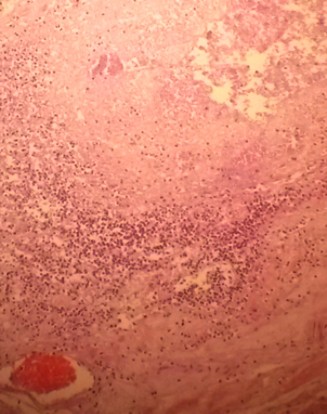

hours from the onset of symptoms. During the procedure, approximately 800 ml of inflammatory peritoneal fluid was identified as well as a distended jejunum and ileum. An intestinal obstruction at the ileocecal valve was found due to a necrotic posterior appendix wrapped around it- this is known as Appendiceal Tie Syndrome (figure 3). The other intestinal loops and the mesentery were normal and there was no evidence of intestinal necrosis. Histopathological macroscopic results reported a cecal appendix measuring 7x1 cm, covered with an opaque serosa and fibrinoid-purulent material. On microscopy, a cecal appendix was observed with areas of necrosis and abundant polymorphonuclear inflammatory infiltrate that involved the entire wall thickness (figure 4). The diagnosis of necrotizing acute appendicitis was confirmed.

Figure 4 - Microscopy of the appendix. Polymorpho-nu- clear inflammatory infiltrate involving the entire thickness of the appendiceal wall. |